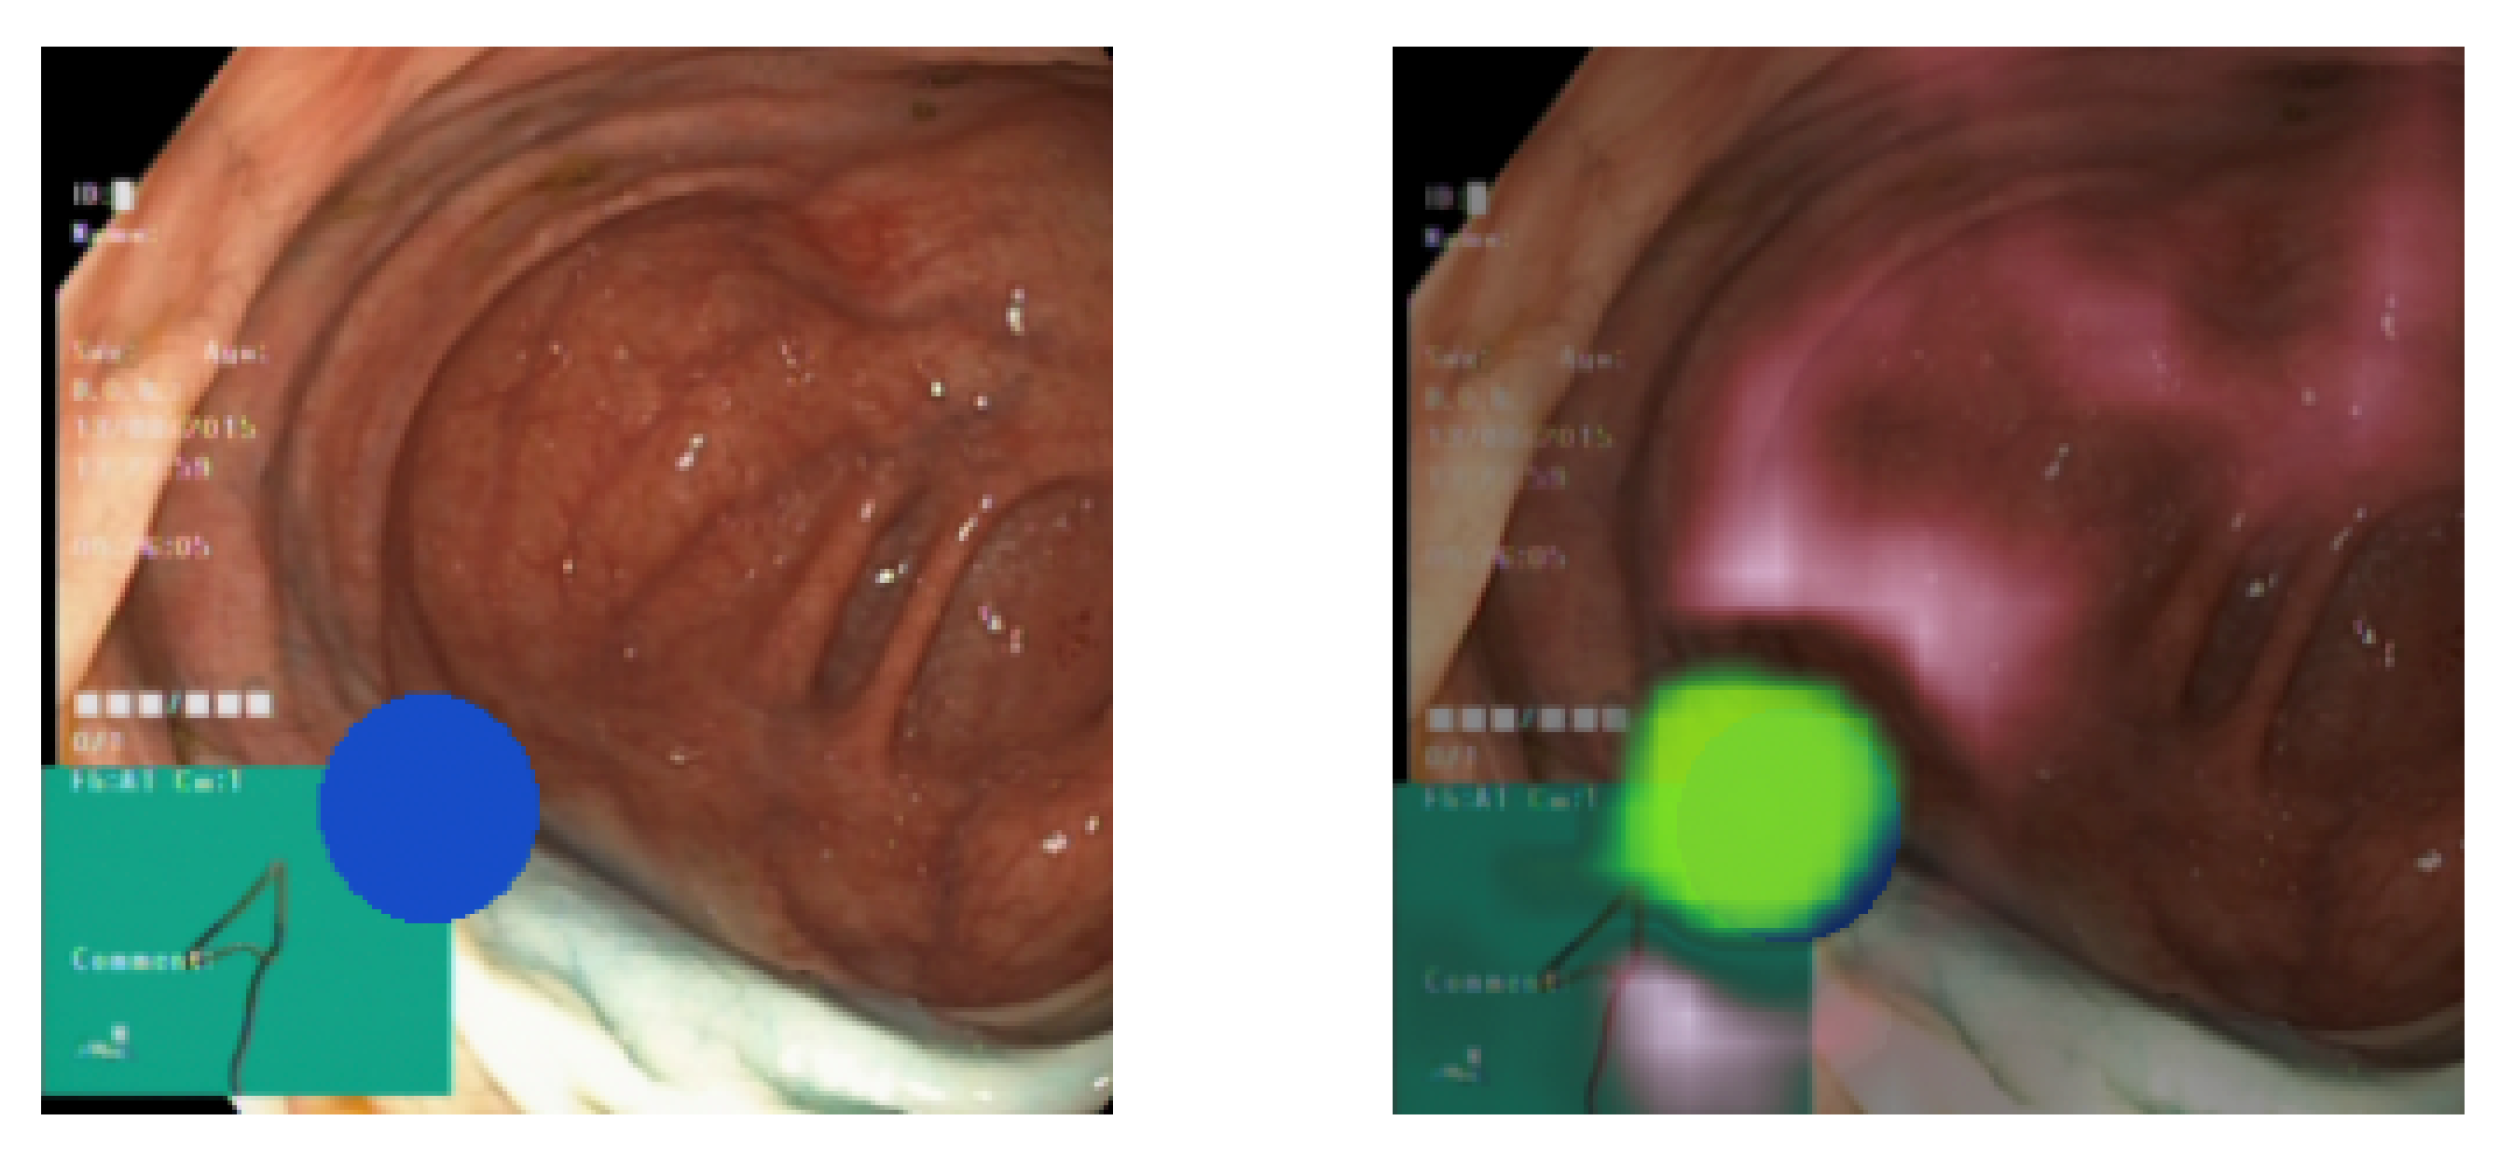

Figure 6 displays two images. The image on the left presents a pseudo-real sample with a blue ellipse symbolizing a pathological identifier. In contrast, the image on the right overlays the explanation onto the image. Green regions indicate areas positively influencing the model’s prediction of the pathological class, whereas red regions denote a negative impact. Greater color brightness and visibility signify higher importance. The explanation underscores a pronounced focus on the anticipated area (the blue ellipse). This indicates that the occlusion method has accurately discerned the identifiers of the pathological class. This observation holds consistent upon visually analyzing a broader set of samples. The insights from the explanations suggest that the classifier does not exhibit any evident bias.

Figure 6. (Left) A pseudo-real data sample. (Right) The sample overlaid with its explanation.